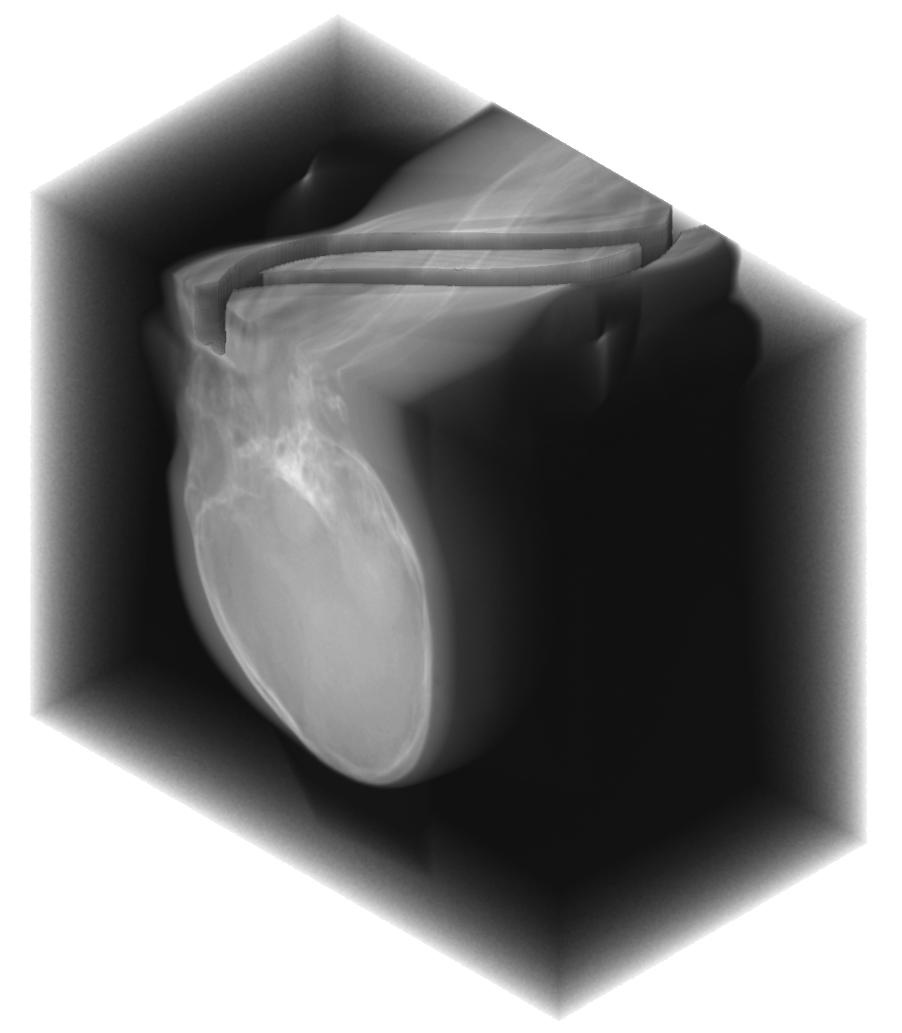

In practice, the complex wavelet transform is an effective tool for extracting singularities from a signal, as previously demonstrated for CT wavefront set extraction in [39]. In images and volumetric data, large-magnitude wavelet coefficients typically occur near jumps and edges. See Fig. 1 for an example of a sinogram containing two metal inserts, where the sum of the absolute values of the wavelet coefficients reveals the corresponding metal boundaries.

We propose a MAR method for projection-domain metal segmentation and inpainting, that uses 3D DT-CWT to find the edges of metals in the 3D sinogram. Fig. 2 shows the full workflow from 3D sinogram to metal artifact reduced reconstruction. The method is explained in detail below.

revealing the locations in the 3D sinogram space corresponding to the largest coefficients. See the 2nd row of Fig. 3 for an illustration of the resulting point cloud for two different 3D sinograms. Then, the result is binarized to by:

We computed the uncorrected FDK reconstruction, the image-domain hard-thresholding–based MAR reconstruction, and the proposed projection-domain complex wavelet MAR reconstruction for datasets (I–V). Fig. 4 shows selected slices from the reconstruction volumes for each dataset, displayed using identical windowing. The quantitative results of the metal segmentation are reported in Table 1 for datasets (I) and (II).

Dataset (I) contains three simulated titanium inserts in an otherwise homogeneous PMMA phantom. Consequently, metal segmentation in both the image and projection domain is expected to be relatively straightforward. As seen in Fig.4, the uncorrected FDK reconstruction exhibits substantial metal artifacts, which are particularly prominent in the axial slices. The HT-MAR method is able to reduce these artifacts to a large extent. However, residual artifacts remain near the metal boundaries as a result of imperfect segmentation. Even after morphological widening of the image-domain segmentation, the mask remains too narrow in some regions while being overly wide in others. This behavior is evidenced by the close-up reconstruction images and the segmentation metrics reported in Table 1. In contrast, the proposed CW-MAR method yields a more accurate projection-domain segmentation, resulting in an almost complete suppression of metal artifacts due to the tighter and more consistent segmentation.